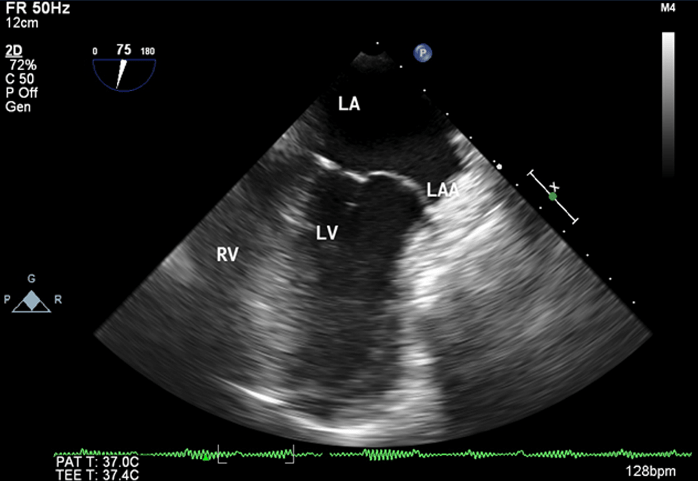

A 22-year-old woman was admitted at our institution in May 2018 with intermittent episodes of chronic atrial fibrillation, angina and dyspnea on exertion New York Heart Association Class-IV. She had three episodes of transient loss of consciousness with no neurological deficits. Notable clinical findings included an intermittently irregular pulse, blood pressure of 90/60 mmHg, cardiomegaly with normal heart sounds and no murmur. The electrocardiogram demonstrated atrial fibrillation, left atrial enlargement, normal axis and voltage. The chest roentgenogram revealed an enlarged cardiac silhouette with a prominent convex bulge of the left upper cardiac border without hilum overlay sign and carinal widening (Figure 1). Transthoracic and transesophageal echocardiogram revealed a giant left atrial aneurysm (8.33 x 7.01 x 4.0 cm) with a wide neck (4.0 cm). The aneurysm extended to the apex of the left ventricle and was entirely intrapericardial and did not show any intraluminal thrombus (Figure 2). The left ventricular diameter and wall motion were within the normal limits. She had moderate dysfunction of the left ventricle (left ventricular ejection fraction=0.35). The interatrial septum and the heart valves were all normal. The visceral layer of the pericardium appeared to be intact.

Figure 2: Transesophageal Echocardiographic midesophageal four chamber view at 0 degree showing aneurysmal left atrial appendage (8.33 x 7.01) with spontaneous echocontrast

LA: left atrium, LV: left ventricle, RV: right ventricle, LAA: left atrial appendage, SEC: spontaneous echocontrast